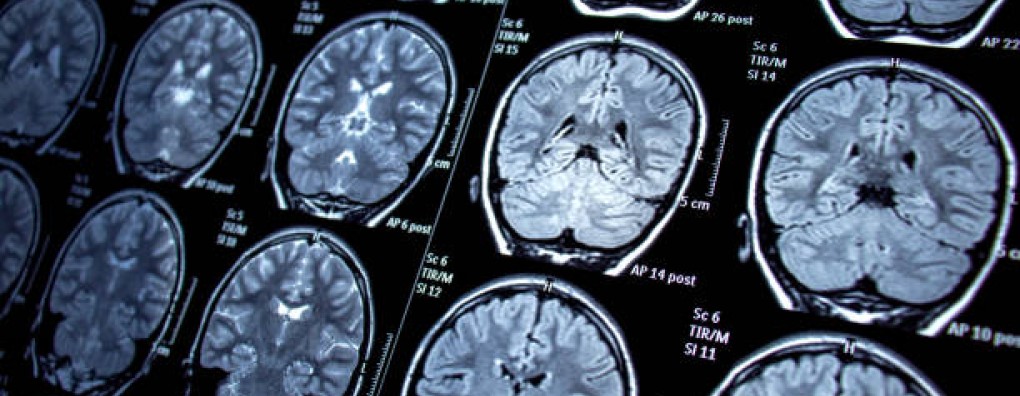

Primaire hersentumoren (waaronder het glioblastoom), maar ook hersenmetastasen van tumoren elders (longkanker, melanoom, borstkanker) zijn vaak niet te genezen. Een brede, palliatieve benadering is noodzakelijk voor de beste kwaliteit van leven. Patiënten met deze tumoren hebben last van gedrags- en karakterveranderingen, hoofdpijn, duizeligheid, epilepsie, uitval van belangrijke lichaamsfuncties inclusief kracht in de ledematen en sufheid door de tumor zelf of door oedeem dat door de tumor(en) ontstaat. Uiteraard leidt dit tot problemen op alle andere domeinen van de palliatieve zorg. Wij spraken alvast met een van de sprekers vanavond: neuro-oncoloog Walter Taal

"Hersenuitzaaiingen komen veel voor. Het is dus belangrijk om te weten wat je kan doen tegen klachten in de laatste levensfase, zoals hoofdpijn, neurologische uitval en epilepsie"

Vooral uitzaaiingen in de hersenen komen steeds vaker voor. Het is dus belangrijk om te weten wat je kan doen tegen klachten in de laatste levensfase, zoals hoofdpijn, neurologische uitval en epilepsie.